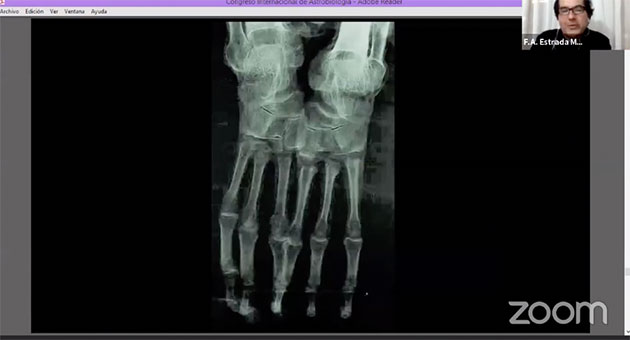

Zu „Material und Methoden“ erläutert Estrada Moreno, dass hierzu Röntgenaufnahmen der besagten Mumien, ebenso wie Aspekte der vergleichenden Anatomie und Analysen mit Infrarot-Spektroskopie zum Einsatz kamen, mit der die Zusammensetzung von Material und Stoffen zerstörungsfrei und von außen durchgeführt werden kann.

Zwar zeigen die Röntgenaufnahmen (Abb. 02 u. 03), dass dieser Körper auf Knochen basiert, doch sind viele dieser Knochen, gerade jene der Gliedmaße, teilweise einfach nur abgeschnitten und stumpf zusammengesetzt wurden. Es fehlen funktionale Gelenke. „Das einzige, was an diesem Körper stimmt, ist die vollständige Wirbelsäule.“

Hier zeigen die Analysen, u.a. Röntgenbilder (Abb. 30), dass dieser Arm nicht aus Ober- und einem Unterarmknochen besteht, sondern es sich um Elle und Speiche eines menschlichen Jugendlichen handelt. Auch die Fingerknochen stammen wohl von einem menschlichen Jugendlichen.

Auch hier zeigt die Röntgenaufnahme (Abb. 32) zum einen den „Metallschmuck“ und zum anderen, dass der Handteller und die Handwurzeln aus (menschlichen) Fingergliedern zusammengepackt wurden. Die echten Handtellerknochen wurden freigelegt, um so die Hand bzw. die Finger größer erscheinen zu lassen. Selbiges gilt für die Finger. Diese wurden durch weitere Fingerknochen verlängert, dies aber teils anatomisch völlig falsch – einige Fingerknochen wurden hier sogar falsch herum angesetzt. Die gesamte Hand (inklusive der zusätzlichen Fingerknochen) ist menschlich.

Hierzu wurden an den Händen jeweils ein Finger und die Daumen entfernt und mit diesen die auf die gleiche Weise bearbeiteten Füße, bzw. deren verbliebene Zehen verlängert, um den Füßen ein zusätzlich exotisches (vermeintlich außerirdisches) Aussehen zu verleihen. Zu erkennen ist dies u.a. daran, dass die Spalten zwischen den Knochen normalerweise viel geringer sein sollten (Abb. 61). Der Umstand, dass dieser Abstand zu groß ist zeigt, dass hier Knochen regelrecht zusammengebaut wurden. Die Spuren dieser Bearbeitung sind erneut auf den Röntgenaufnahmen zu erkennen. Anhand eines Vergleich von Röntgenaufnahmen normaler (vollständiger) Hände (Abb. 62, 63 r. u. m) mit Marias Füßen (Abb. 63, 63 l.) verdeutlichen die Schaubilder (Abb. 62, 63), welche Knochen wo entfernt und hinzugefügt wurden.

Ab Timecode 1.06:12 geht Moreno nochmals auch die Röntgenanalysen einiger Mumien ein und zeigt, wie sich die unterschiedlichen Materialien (Aire = Luft, Grasa = Fett, Agua = Wasser, Hueso = Knochen und Metall, s. Abb. 64) in der Röntgenbetrachtung abbilden.